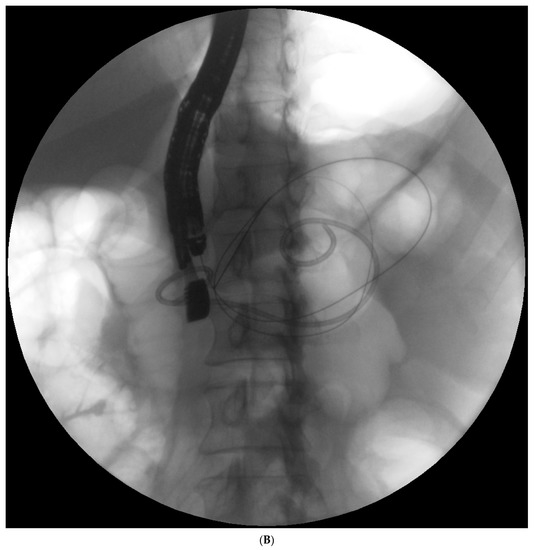

Endotherapy for post-inflammatory pancreatic and peripancreatic fluid collections (Figure 1A–L) is a recognized, minimally invasive treatment method [6][7][8]. Transpapillary endoscopic drainage involves accessing the collection through the major duodenal papilla if the main pancreatic duct communicates with the collection [6][10][11][12][13]. Active transpapillary drainage involves the introduction of a nasal drain and a pancreatic stent through the major duodenal papilla with their distal ends passing through the site of disruption into the lumen for the fluid collection [6][10][11][12][13]. Subsequently, the collection is rinsed with a saline solution through the drain. Passive transpapillary drainage involves the introduction of a stent into the main pancreatic duct, which is important for endotherapy for main pancreatic duct disruption [6][10][11][12][13]. The size and length of the pancreatic stent should be selected individually according to the fluoroscopic image of the main pancreatic duct during endoscopic retrograde pancreatography. Main pancreatic duct stenting (passive transpapillary drainage) is designed to ensure the free outflow of pancreatic juices by physiological means into the duodenal lumen and, consequently, to prevent the juices from escaping through the injured duct into the collection, thus increasing its volume. Moreover, inserting a stent into the pancreatic duct (Figure 2A–C) is supposed to create conditions that promote healing and stop pancreatic juice leakage by bridging the disrupted part of the duct.

Figure 1. (A–L) Endoscopic treatment of walled-off pancreatic necrosis. In the second week of acute necrotizing pancreatitis, the acute necrotic collection (A) is visible in the abdominal contrast-enhanced computed tomography (CECT), which evolved in the sixth week of the illness duration into the symptomatic walled-off pancreatic necrosis (B). Patient qualified for endoscopic treatment (C–F) transmural drainage using the self-expanding metal stent (C,D) and endoscopic necrosectomy (E,F) was performed. In the second week of endotherapy, the endoscopic retrograde pancreatography (G–J) was performed. During pancreatography, the complete pancreatic duct disruption was stated (G–I) and transpapillary drainage was carried out (J). After achieving the treatment’s success and the complete regression of the necrotic collection, the transpapillary stent was observed in the bottom of the collection via the endoscopic view from the stomach’s side through the transmural stent (K). Control CECT confirmed the total regression of the collection (L).

Figure 2. (A–C). Endoscopic treatment of the pancreatic pseudocyst. Transmural drainage using plastic stents was performed (A,B). The endoscopic retrograde pancreatography (C) was performed. During the pancreatography, complete disruption of the pancreatic duct was stated (C). Transpapillary access to the pseudocyst was achieved (C). Transmural access to the same collection was stated (A,B).